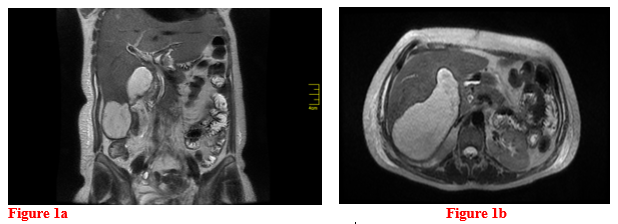

The patient progressed adequately after the procedure, and completing antibiotic treatment with a dual regimen of high-dose carbapenem and glycylcycline, in addition to anthelmintic management with albendazole for 10 days, remaining asymptomatic, therefore discharge was defined (Figure 1a &1b).

Figure 1a&1b Magnetic resonance cholangiography: (t2 coronal right axial left section) Post cholecystectomy status, hepatic sub capsular collection that extends from the surgical bed between segments 5 and 6, without blood remains, mild ectasia of the extrahepatic bile duct with linear image inside suggestive of hepatobiliary endoprosthesis. Mild biliary ectasia, no gallstones identified.